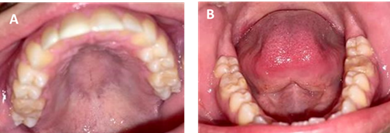

Through clinical and radiographic examination, MIH in the first permanent molars and the presence of a supernumerary in the mandibular incisor region were concluded as a diagnostic impression. The indicated treatment plan is prophylaxis, restoration with ionomeric glass, sealants of pits and fissures in DU 1.6, 2.6, 3.6, 4.6 and topical application of fluoride. Periodic six-monthly check-ups were indicated at the beginning of the treatment to review the restorations for a period of three years. At the age of 10, it was decided to place composite resins. From that date on, visits to the dentist were made annually. Currently, at age 21, the restorations with composite resins that were placed 11 years ago are still in the mouth. They show changes in color and slight wear of the occlusal surface, but the patient does not report any symptoms (figure 4).

At the age of 10, it was decided to use composite resins with absolute isolation, and the patient has since been under the care of their treating dentist. Over this 11-year period, there have been gradual changes in the color of the restorations, but no sensitivity nor discomfort has been reported in any of the units. According to the literature, the use of resins is a viable option with high success rates when placed under isolation with a rubber dam to ensure proper humidity control (22.